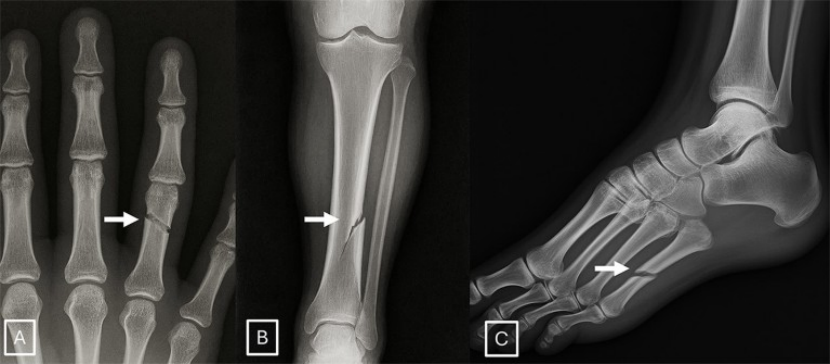

AI生成的X光片若被纳入训练数据集可能会对分析医疗数据的AI工具产生偏差。图片来源:北美放射学会(RSNA)

该研究的作者们设计了一项互动测试,旨在教会研究人员如何辨别AI生成的X光扫描图像与真实的图像。这项测试涵盖了AI生成放射影像的一些典型特征,例如骨骼表面过于光滑、脊柱呈现出不自然的笔直形态等。作者们指出,除了对放射科医生进行相关培训外,采用数字水印等技术,以及建立由政府机构主导的监管框架,都有助于人们更轻松地识别出真实的图像。